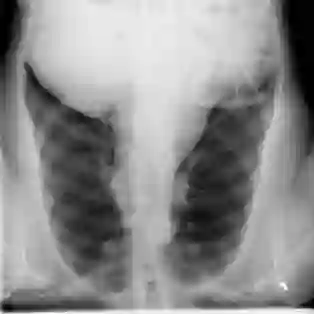

The COVID-19 disease was first discovered in Wuhan, China, and spread quickly worldwide. After the COVID-19 pandemic, many researchers have begun to identify a way to diagnose the COVID-19 using chest X-ray images. The early diagnosis of this disease can significantly impact the treatment process. In this article, we propose a new technique that is faster and more accurate than the other methods reported in the literature. The proposed method uses a combination of DenseNet169 and MobileNet Deep Neural Networks to extract the features of the patient's X-ray images. Using the univariate feature selection algorithm, we refined the features for the most important ones. Then we applied the selected features as input to the LightGBM (Light Gradient Boosting Machine) algorithm for classification. To assess the effectiveness of the proposed method, the ChestX-ray8 dataset, which includes 1125 X-ray images of the patient's chest, was used. The proposed method achieved 98.54% and 91.11% accuracies in the two-class (COVID-19, Healthy) and multi-class (COVID-19, Healthy, Pneumonia) classification problems, respectively. It is worth mentioning that we have used Gradient-weighted Class Activation Mapping (Grad-CAM) for further analysis.

翻译:COVID-19 疾病在中国武汉首次发现,并迅速蔓延到全世界。在COVID-19 流行病后,许多研究人员开始寻找一种方法,利用胸前X光图像诊断COVID-19 。早期诊断该疾病可以大大影响治疗过程。在本篇文章中,我们提出了一种比文献中报告的其他方法更快和更准确的新方法。拟议方法使用DenseNet169 和移动网络深神经网络的组合来提取病人X光图像的特征。在使用单向特征选择算法后,我们改进了最重要的特征。然后,我们将选定特征用作对光GBM(轻度推动机)算法的投入。为评估拟议方法的有效性,使用了ChestX-光8 数据集,其中包括病人胸部的1125 X光图像。拟议方法在两类(COVID-19,健康价值)和多级(COVID-19)中达到了98.54%和91.11%的缩略图。我们分别使用了“高度”的GRAMA-GRA级(C) 分别用于健康等级分析。